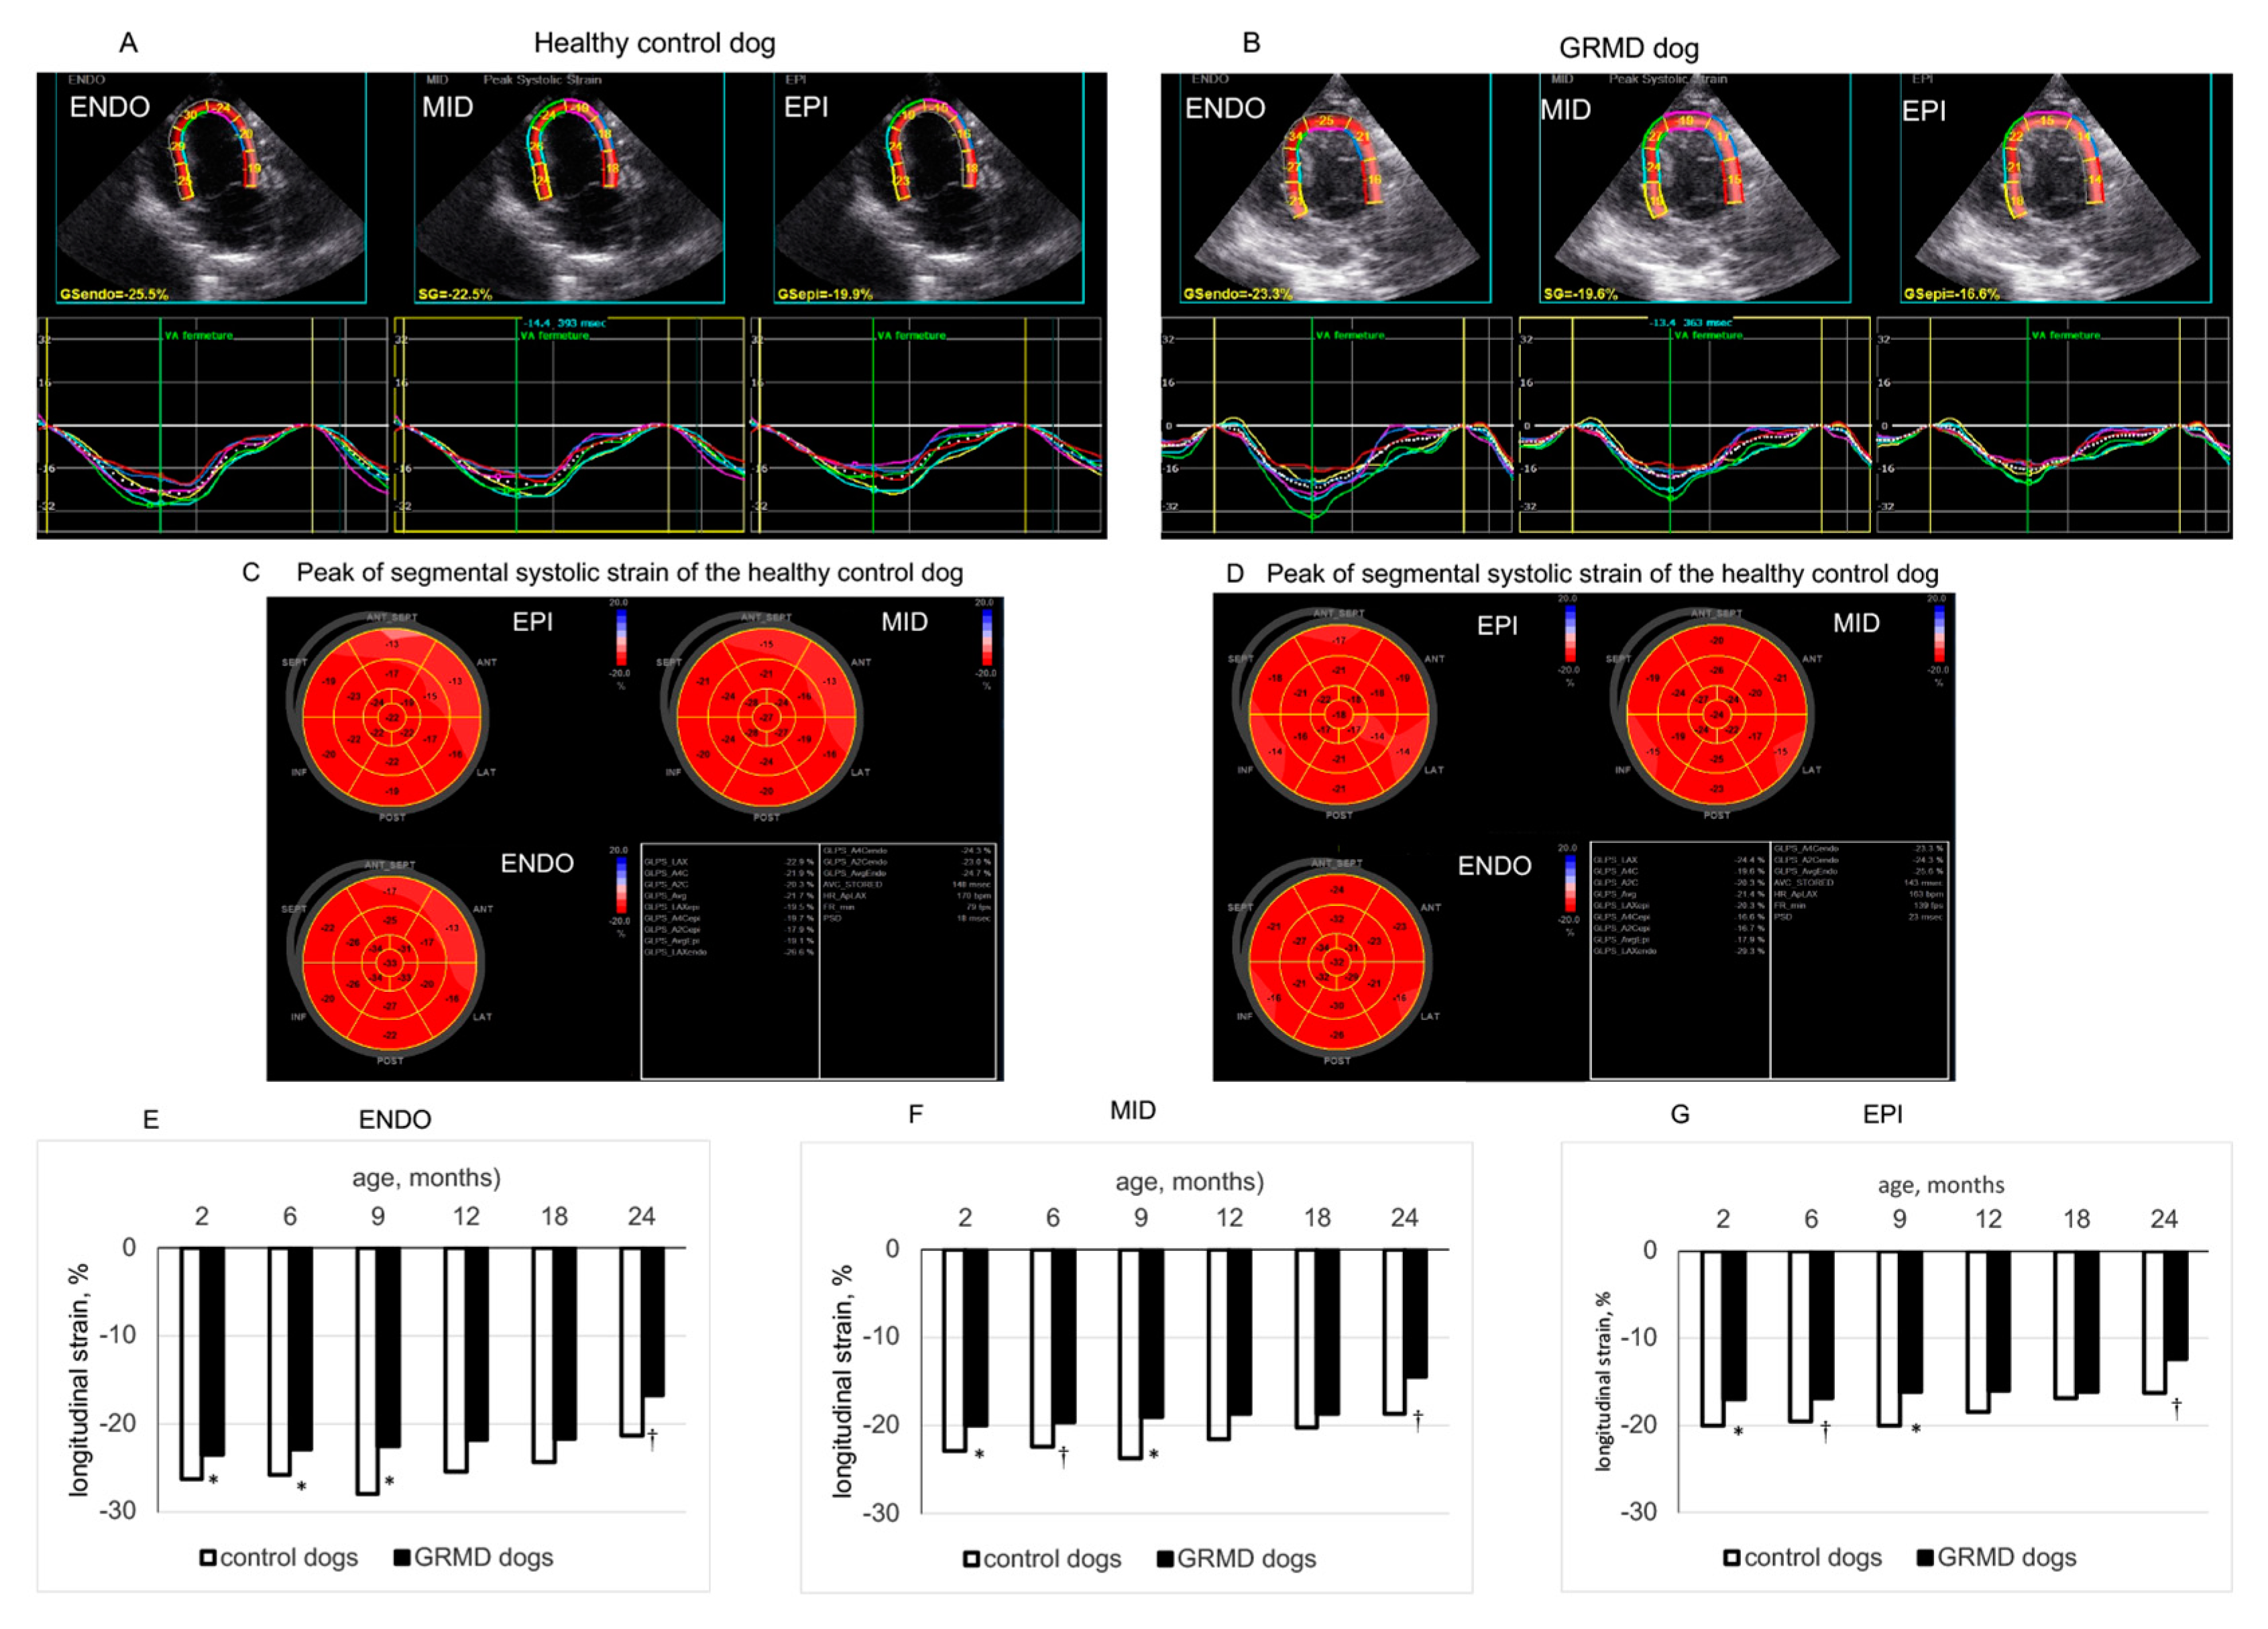

3.3. Changes in LS in the Three LV Wall Layers Analyzed by 2D-STE from the Three Apical Views in GRMD and Healthy Control Dogs at Different Ages

| 3C endocardial LS | Control | −28.8 ± 1.9 | −26.2 ± 1.7 | −25.8 ± 0.9 | −26.1 ± 0.8 | −23.5 ± 2.4 | −21.7 ± 1.1 | 0.0702 | 0.0010 |

| GRMD | −22.6 ± 0.6 † | −22.8 ± 0.8 * | −22.1 ± 1. 0 * | −21.9 ± 0.7 * | −22.1 ± 1.2 | −19.5 ± 1.7 | 0.3076 | ||

| 3C middle layer LS | Control | −24.0 ± 1.8 | −22.8 ± 1.5 | −22.3 ± 0.8 | −22.9 ± 1.0 | −20.3 ± 2.2 | −18.3 ± 0.6 | 0.1366 | 0.0007 |

| GRMD | −18.9 ± 0.5 † | −19.2 ± 0.6 * | −19.0 ± 0.7 * | −18.7 ± 0.8 * | −18.9 ± 0.9 | −16.7 ± 1.6 | 0.4422 | ||

| 3C epicardial LS | Control | −19.9 ± 1.7 | −19.9 ± 1.5 | −19.3 ± 0.7 | −20.1 ± 1.3 | −17.6 ± 2.1 | −15.5 ± 0.4 | 0.2452 | 0.0010 |

| GRMD | −15.9 ± 0.5 † | −16.3 ± 0.5 † | −16.5 ± 0.7 | −16.2 ± 0.6 * | −16.2 ± 0.7 | −14.4 ± 1.5 | 0.5367 | ||

| 4C endocardial LS | Control | −26.3 ± 1.3 | −25.7 ± 1.2 | −27.9 ± 2.1 | −25.4 ± 1.5 | −24.3 ± 0.6 | −21.4 ± 0.4 | 0.0881 | 0.0030 |

| GRMD | −23.5 ± 0.6 * | −22.9 ± 0.5 * | −22.5 ± 1.0 * | −21.7 ± 0.9 | −21.7 ± 1.3 | −16.8 ± 0.7 † | 0.0002 | ||

| 4C middle layer LS | Control | −22.8 ± 1.3 | −22.3 ± 0.9 | −23.7 ± 1.5 | −21.6 ± 1.2 | −20.3 ± 0.4 | −18.7 ± 0.5 | 0.0863 | 0.0034 |

| GRMD | −20.0 ± 0.5 * | −19.6 ± 0.4 † | −19.1 ± 0.9 * | −18.5 ± 0.8 | −18.7 ± 1.0 | −14.4 ± 0.7 † | 0.0002 | ||

| 4C epicardial LS | Control | −20.8 ± 1.4 | −19.6 ± 0.8 | −20.1 ± 1.0 | −18.4 ± 1.0 | −17.0 ± 0.5 | −16.3 ± 0.6 | 0.1023 | 0.0069 |

| GRMD | −17.0 ± 0.5 * | −16.9 ± 0.4 † | −16.2 ± 0.8 * | −16.0 ± 0.7 | −16.2 ± 0.8 | −12.5 ± 0.7 † | 0.0006 | ||

| 2C endocardial LS | Control | −26.0 ± 0.6 | −25.9 ± 0.9 | −25.2 ± 1.2 | −25.6 ± 1.0 | −22.6 ± 2.0 | −22.1 ± 1.2 | 0.0277 | 0.0054 |

| GRMD | −23.2 ± 0.5 † | −22.6 ± 0.5 † | −21.8 ± 0.7 * | −20.0 ± 0.8 † | −19.7 ± 1.3 | −19.4 ± 1.3 | 0.0006 | ||

| 2C middle layer LS | Control | −22.7 ± 0.6 | −22.2 ± 0.9 | −21.5 ± 1.2 | −21.7 ± 0.7 | −19.7 ± 1.4 | −19.6 ± 0.9 | 0.0746 | 0.0035 |

| GRMD | −19.5 ± 0.4 † | −19.6 ± 0.4 † | −19.0 ± 0.7 | −17.4 ± 0.7 † | −17.6 ± 1.2 | −16.7 ± 1.1 | 0.0088 | ||

| 2C epicardial LS | Control | −20.1 ± 0.5 | −19.1 ± 1.0 | −18.4 ± 1.5 | −18.3 ± 0.8 | −17.2 ± 1.1 | −17.5 ± 0.7 | 0.1672 | 0.0032 |

| GRMD | −16.4 ± 0.4 † | −17.2 ± 0.4 * | −16.8 ± 0.7 | −15.3 ± 0.6 * | −15.8 ± 1.0 | −14.4 ± 1.0 | 0.0398 | ||